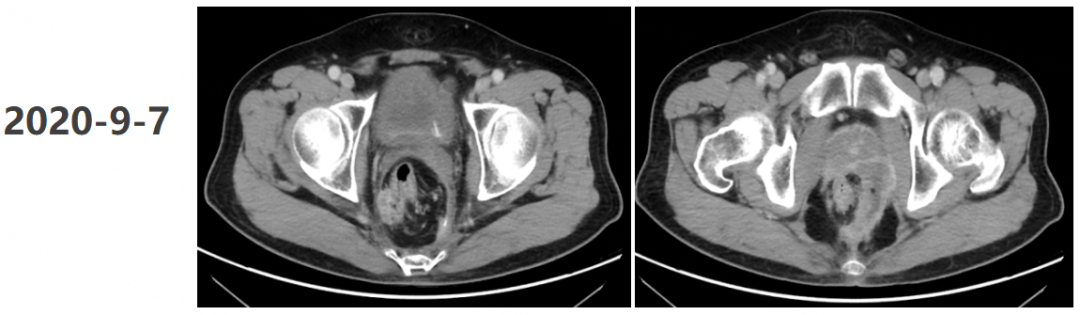

2020年11月20日,再次腹盆腔CT增强:“直肠癌术后+前腹壁造瘘术”后改变,局段直肠壁增厚伴邻近筋膜增厚、腹膜反折处结节样增厚,需考虑肿瘤复发可能,较前片(2020年9月7日)略有进展,较前片(2020年4月10日)明显进展。疗效评估为疾病进展(PD)。

2020年11月21日至今,予三线靶向呋喹替尼联合信迪利单抗免疫治疗,具体方案:呋喹替尼(3mg po d1-14)+信迪利单抗(200mg d1,q21d)。

2021年5月13日开始每3个月复查1次,疗效评估均为持续PR。